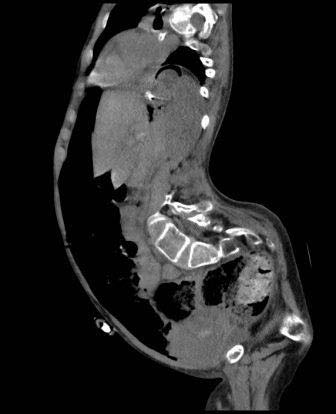

Upon arrival, he was hypotensive complaining of severe abdominal pain radiating to the back with new-onset paresthesia of his bilateral lower Extremities. The duration of symptoms was approximately two hours before evaluation in our institution. The patient was not in congestive heart failure. A CT Angiogram of the abdomen and pelvis was obtained and revealed a ruptured 7.5cm infrarenal AAA with contrast extravasations into the retro peritoneum. There was a significant contrast enhancement of the inferior vena cava (IVC) suggesting the presence of ACF (Fig 1). The aneurysm neck was highly angulated and approximately 12mm long. The patient was taken to our hybrid operating room (OR) for further treatment. Wire access was obtained through bilateral femoral artery cut-downs, and a Medtronic 26mm Talent main body device with AneuRxiliac limbs was placed with preservation of both hypo gastric arteries. Aortography revealed a large Type I end leak (EL) and persistent ACF ( Fig 2, Fig 3). A large Palmaz stent was mal-deployed at the neck and was, therefore, moved proximally and fully deployed in the thoracic aorta. A second well deployed Palmaz stent failed to completely resolve the Type I EL as did placement of a proximal aortic cuff with intentional coverage of the left renal artery. The femoral veins were cannulated, and a large compliant balloon was inflated in the IVC to occlude the ACF with a resultant significant decrease in the Type I EL suggesting that closing the fistula by placing a stent graft within the inferior vena cava (IVC) at the bifurcation might resolve the large end leak. A sufficiently large stent graft was not available at the time so the patient was transferred to the ICU where he remained stable until he returned to the operating room on the second post-operative day. The ACF was excluded by a deployment of a Gore TAG device within the IVC followed by placement of bilateral iliac vein reversed Gore 16x20 limbs (Fig 4). Aortography demonstrated a small Type III end leak which was not treated at this point.